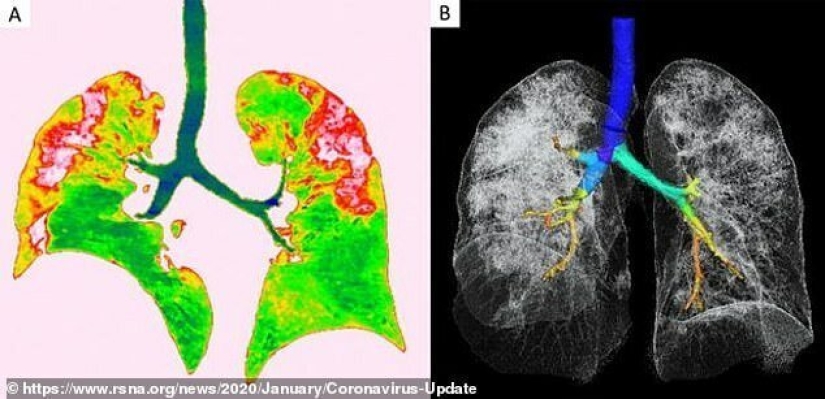

Estas son fotos de una mujer de 54 años que, al regresar de Wuhan, fue diagnosticada con neumonía viral grave. Durante el tratamiento, los médicos le dieron oxígeno y antibióticos.